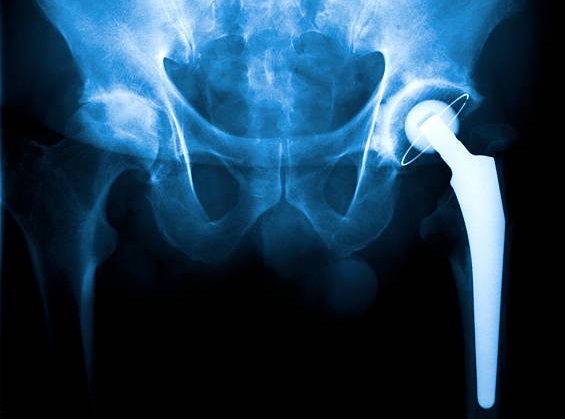

Your surgeon will use an artificial joint to replace your complete hip during a total hip replacement. The femur, the top bone of your thigh, and the acetabulum, the socket it fits into, are both replaced. Total hip replacements account for almost all hip replacement procedures.

Patients with extensive hip joint damage from fractures, degenerative diseases, or arthritis might benefit greatly from hip replacement surgery, a highly successful orthopedic technique that relieves pain and restores mobility. The hip joint's damaged areas, such as the worn-out bone and cartilage, are carefully removed during the treatment and replaced with artificial implants composed of sturdy materials like ceramic, metal, or premium plastic. These prosthetic parts enable for painless and fluid mobility by simulating the hip's natural ball-and-socket function. Usually carried out under regional or general anesthesia, the procedure can be completed with less invasive methods that encourage quicker recovery, less scarring, and faster healing. Therefore get in touch with us now because we provide Best Hip Replacement Surgery in Panvel.